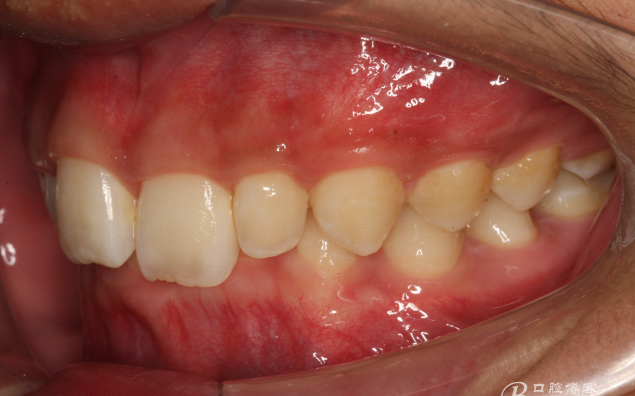

圖3.左側(cè)位咬合影像